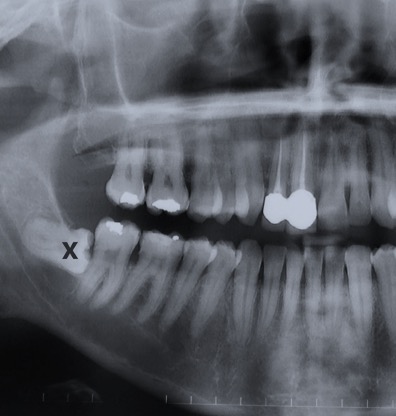

Estrazione di denti del giudizio . È l’intervento più frequente in chirurgia orale. Tra le indicazioni per l’avulsione possiamo menzionare la mancanza di spazio nella mascella o nella mandibola per la sua corretta eruzione, il suo orientamento anomalo responsabile di infiammazioni alle mucose o danni ai molari vicini, le necessità ortodontiche.

Estrazioni dentali complesse. Un’estrazione dentale può essere complicata non solo da un punto di vista pratico chirurgico ma anche nella gestione di casi in cui i pazienti assumono farmaci o presentano malattie sistemiche.